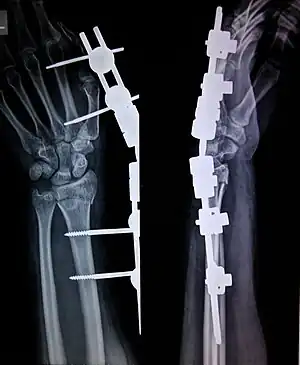

X-ray image of an external fixator being used to stabilise a Colles' fracture involving the Radius bone

External fixation is a surgical treatment wherein Kirschner pins and wires are inserted and affixed into bone and then exit the body to be attached to an external apparatus composed of rings and threaded rods — the Ilizarov apparatus, the Taylor Spatial Frame, and the Octopod External Fixator — which immobilises the damaged limb to facilitate healing.[1] As an alternative to internal fixation, wherein bone-stabilising mechanical components are surgically emplaced in the body of the patient, external fixation is used to stabilize bone tissues and soft tissues at a distance from the site of the injury.